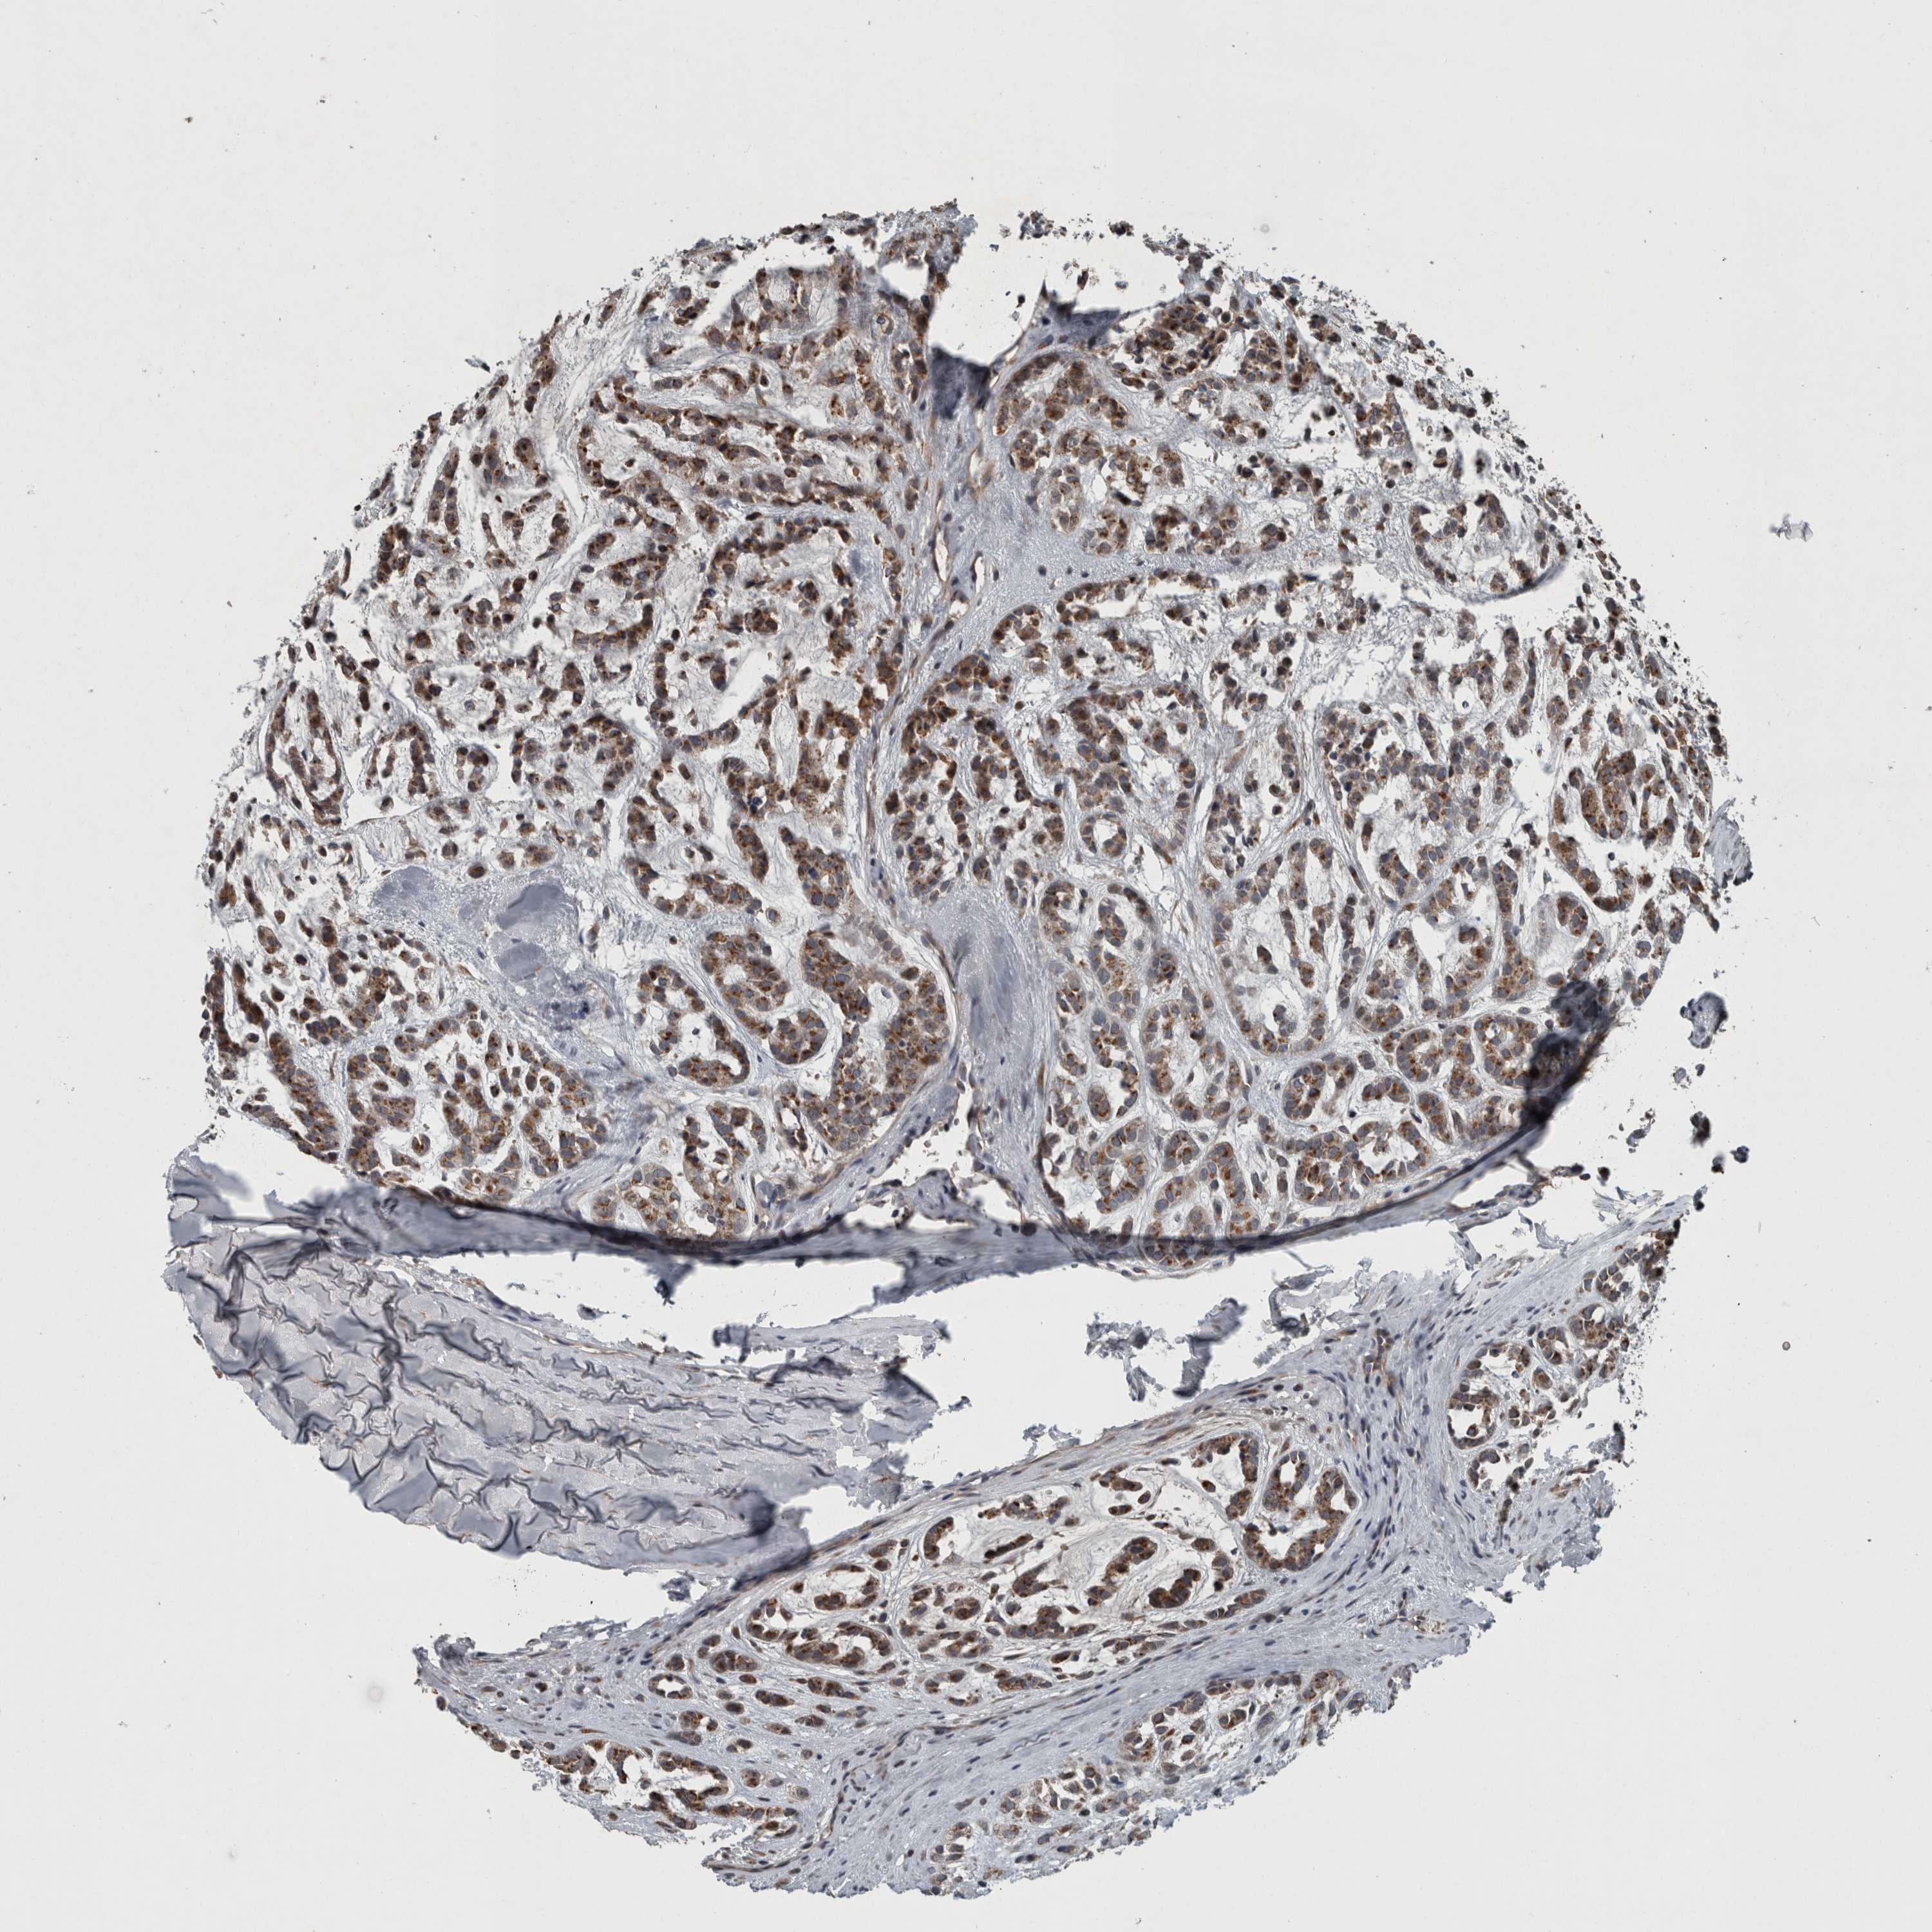

HEAD AND NECK CANCER - Protein expressioni

A mouse-over function shows sample information and annotation data. Click on an image to view it in a full screen mode. Samples can be filtered based on level of antibody staining by selecting one or several of the following categories: high, medium, low and not detected. The assay and annotation is described here.

Antibody stainingi

Antibody staining in the annotated cell types in the current human tissue is reported as not detected, low, medium, or high, based on conventional immunohistochemistry profiling in selected tissues. This score is based on the combination of the staining intensity and fraction of stained cells.

Each image is clickable and will lead to virtual microscopy that enables deeper exploration of all samples and also displays staining intensity scores, fraction scores and subcellular localization as well as patient and tissue information for each sample.

Antibody HPA025816

Staining

High

Medium

Low

Not detected

Intensity

Strong

Moderate

Weak

Negative

Quantity

>75%

75%-25%

<25%

None

Location

Nuclear

Cytoplasmic/membranous

Cytoplasmic/membranous,nuclear

Squamous cell carcinoma, NOS

Squamous cell carcinoma, metastatic, NOS

Adenocarcinoma, NOS

Adenoma, NOS